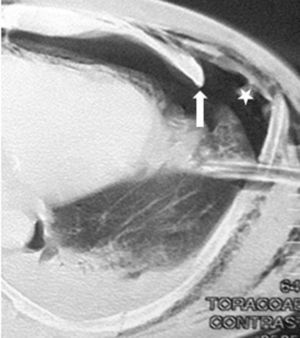

Caso 2Paciente masculino de 51 años, quien recibió trauma cerrado en hemitórax izquierdo luego de ser envestido por un toro. Recibió manejo inicial en hospital rural, pero por persistir con dolor en hemitórax izquierdo y sensación de disnea consulta a la institución. Al examen físico no se evidenció respiración paradójica, ni enfisema subcutáneo, ni hipoventilación ni agregados pulmonares. Se le tomó tomografía computada de tórax que mostró fractura desplazada de 3 arcos costales izquierdos con hemotórax; por los hallazgos clínicos y tomográficos se le practicó osteosíntesis de reja costal con el sistema STRACOS® con la utilización de sello de agua postoperatorio sin complicaciones, se incorporó a su vida laboral 20 días posteriores al trauma. No hay seguimiento de la función pulmonar por pérdida del paciente (figs. 3 y 4).

Paciente masculino de 30 años quien sufrió accidente de tránsito en moto, en calidad de conductor. Presenta trauma cerrado de abdomen, trauma cráneoencefálico con pérdida de estado de conciencia y fracturas faciales. Al examen físico presentó: disminución de ruidos respiratorios en bases pulmonares, sin agregados, dolor y crepitación a la palpación de reja costal anterior y superior izquierda. Abdomen sin defensa muscular. Se realizó tomografía computada de tórax, donde se evidenció contusión pulmonar del lóbulo inferior izquierdo, con fracturas costales de la segunda a la séptima izquierda, con tercer y cuarto arco costal fracturado en 3 fragmentos. Recibió manejo con intubación orotraqueal para manejo de la vía aérea por las fracturas faciales y por evidencia de tórax inestable con respiración paradójica del segmento costal fracturado, por lo que se le practicó osteosíntesis de la reja costal con el sistema MATRIX RIB® con placas premoldeadas de 10 orificios, y tornillos bloqueados bicorticales, con la utilización de sello de agua en el postoperatorio, sin complicaciones. El paciente es extubado 15 días después, y debido al trauma craneoencefálico no puede retornar a las labores diarias. No hay seguimiento de la función pulmonar por pérdida del paciente (figura 5 para el caso 3 y figura 6 para el caso 4).